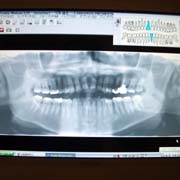

[デジタルレントゲン]

従来型と比べ、大幅に被曝量を抑えております。

デジタルなので、現像までの時間も短く、鮮明な画像により、さらに正確な診断が可能です。

患者様は、チェアーにお座り頂いたままで、ご自身の鮮明なレントゲン画像をご覧になる事が出来ます。

(上記画像の掲載につきましては、患者様よりご了承を頂いております)